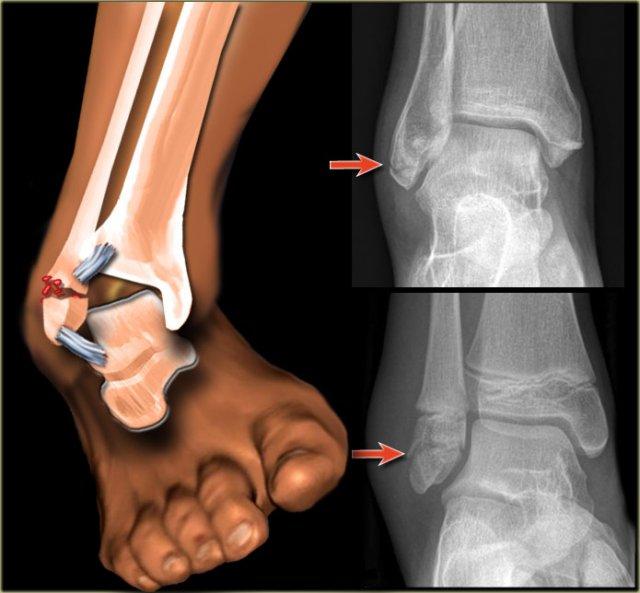

Hình ảnh X-quang cho thấy một gãy xương Weber B điển hình.

Hãy quan sát kỹ hình ảnh trước rồi tiếp tục đọc.

Bạn có nhận ra đây là giai đoạn nào không?

Đây là tổn thương Weber B giai đoạn 4.

Lưu ý rằng cả 4 giai đoạn đều có thể nhìn thấy:

- Đứt dây chằng chày mác trước – biểu hiện bằng sự giãn rộng khoảng cách giữa đầu xa xương chày và xương mác (khoảng sáng bên ngoài).

- Gãy xương mác chéo ở mức khớp chày mác – tức là gãy kiểu Weber B.

- Gãy xương Tertius – thấy trên phim thẳng (mũi tên đỏ) và trên phim nghiêng (mũi tên vàng).

- Rupture của dây chằng bên trong – được thấy như sự mở rộng của khoảng cách giữa mắt cá chân trong và xương sên (khoảng sáng trong)

Những hình ảnh này cho thấy một gãy xương Weber B điển hình giai đoạn 4.

Có một đường gãy chéo của xương mác.

Có một gãy giật bong mắt cá sau và một gãy giật bong mắt cá trong.